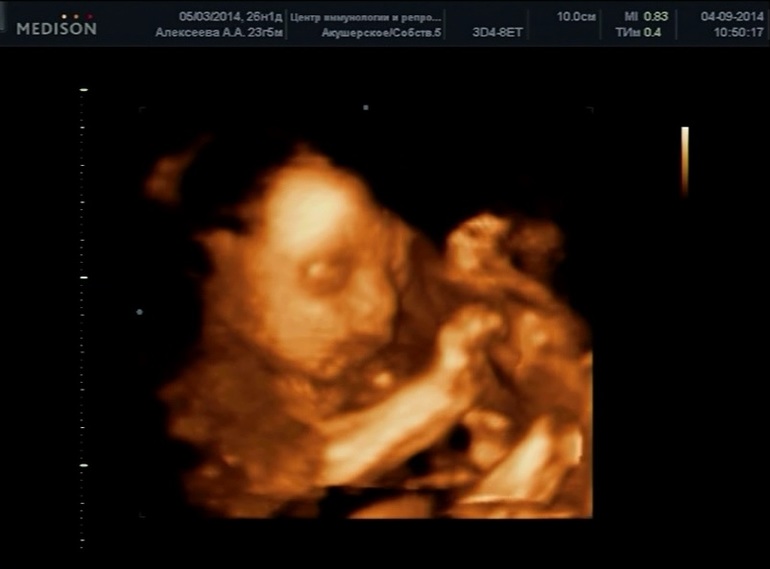

И фото узи на тех же неделях. Моя ежевичка сладкая

Она на этих 3д очень на мужа похожа! Но это нам повезло с аппаратом, качество хорошее, а на другом вообще ерунда была

Которое хорошее в ЦИРЕ у Справцевой, про нее тут много пишут. А фиговое у нас на районе